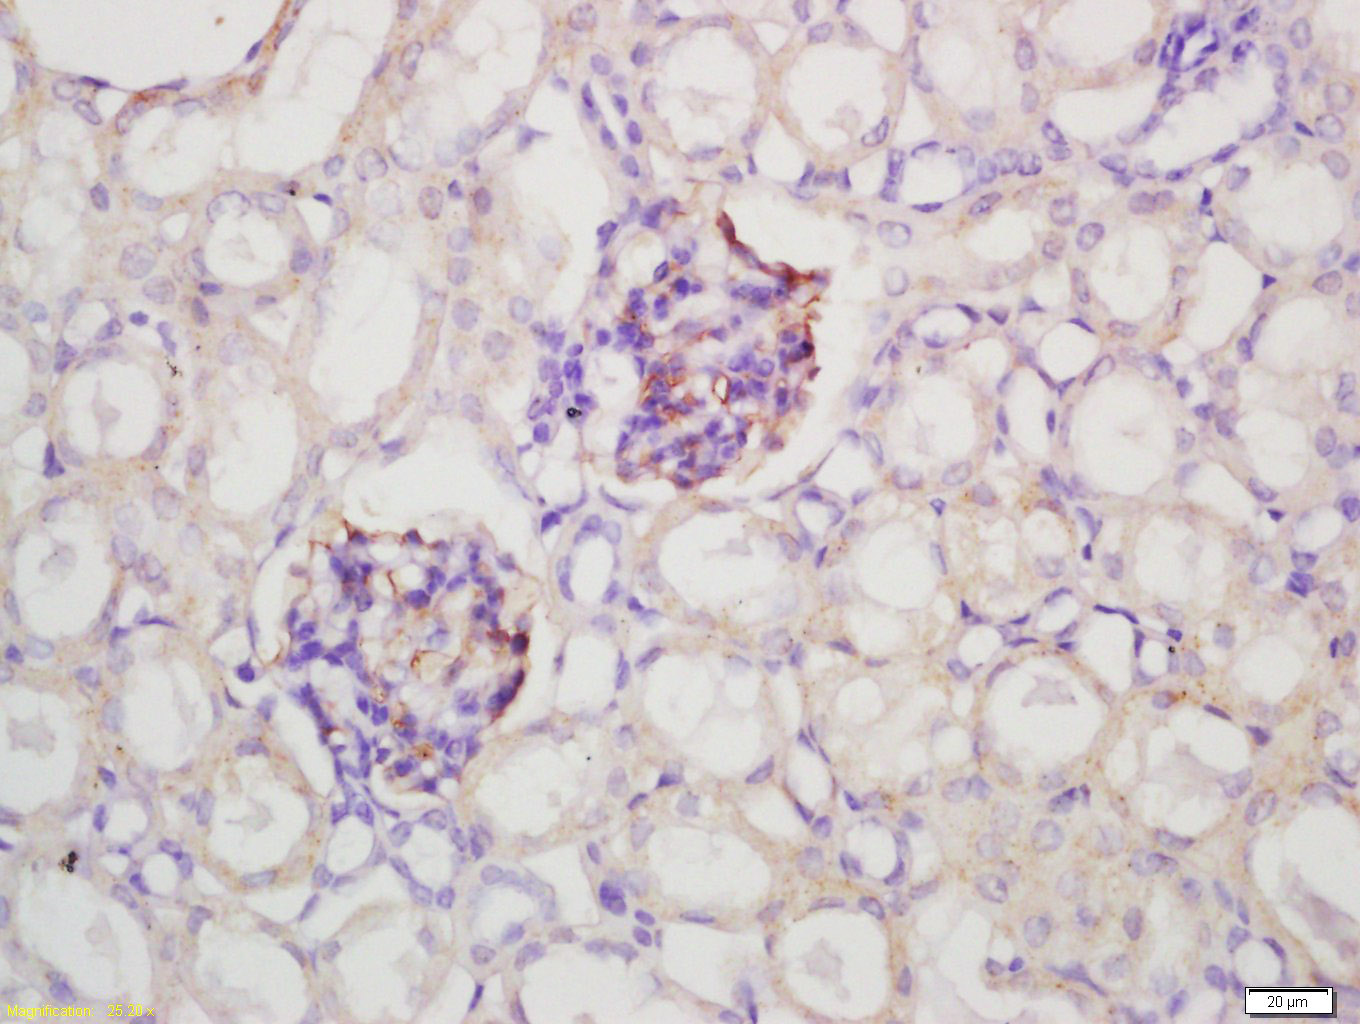

Tissue/cell: rat lung carcinoma; 4% Paraformaldehyde-fixed and paraffin-embedded; Antigen retrieval: citrate buffer ( 0.01M, pH 6.0 ), Boiling bathing for 15min; Block endogenous peroxidase by 3% Hydrogen peroxide for 30min; Blocking buffer (normal goat serum,C-0005) at 37℃ for 20 min; Incubation: Anti-GGA2 Polyclonal Antibody, Unconjugated(bs-13344R) 1:200, overnight at 4°C, followed by conjugation to the secondary antibody(SP-0023) and DAB(C-0010) staining